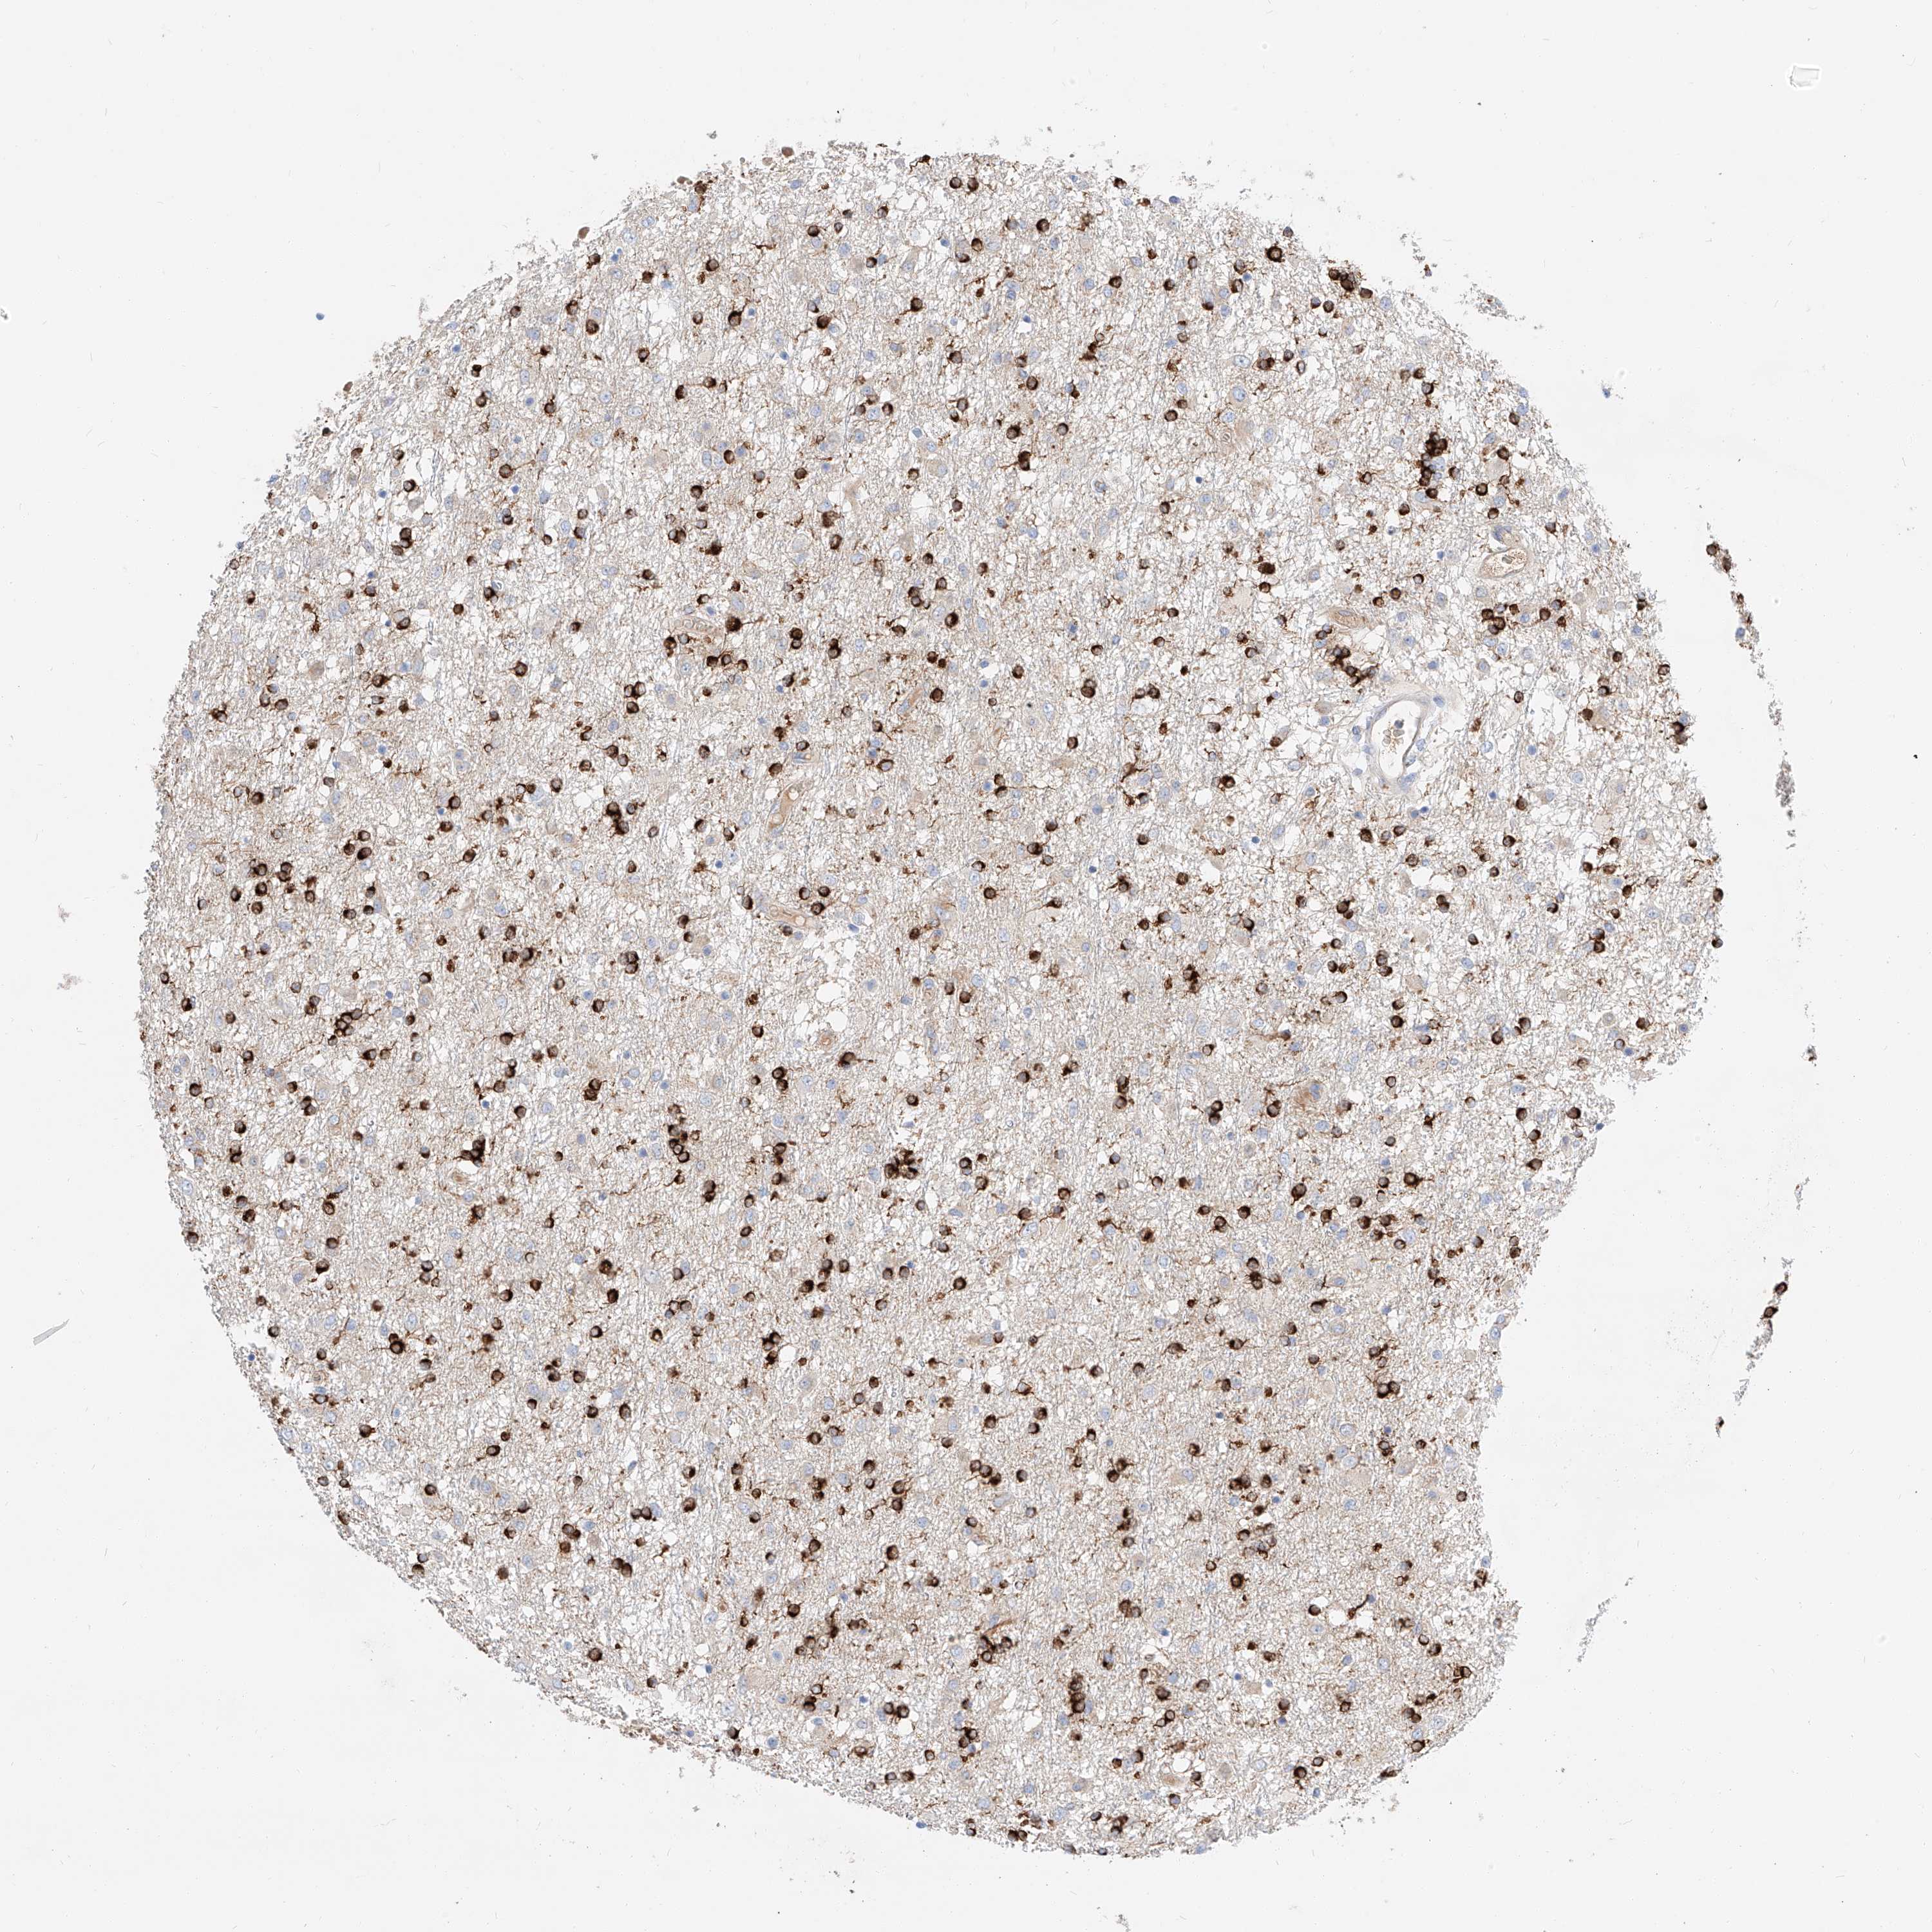

GLIOMA - Protein expressioni

A mouse-over function shows sample information and annotation data. Click on an image to view it in a full screen mode. Samples can be filtered based on level of antibody staining by selecting one or several of the following categories: high, medium, low and not detected. The assay and annotation is described here.

Note that samples used for immunohistochemistry by the Human Protein Atlas do not correspond to samples in the TCGA dataset.

Antibody stainingi

Antibody staining in the annotated cell types in the current human tissue is reported as not detected, low, medium, or high, based on conventional immunohistochemistry profiling in selected tissues. This score is based on the combination of the staining intensity and fraction of stained cells.

Each image is clickable and will lead to virtual microscopy that enables deeper exploration of all samples and also displays staining intensity scores, fraction scores and subcellular localization as well as patient and tissue information for each sample.

Antibody HPA029712

Antibody HPA029713

Staining

High

Medium

Low

Not detected

Intensity

Strong

Moderate

Weak

Negative

Quantity

>75%

75%-25%

<25%

None

Location

Nuclear

Cytoplasmic/membranous

Cytoplasmic/membranous,nuclear

Glioma, malignant, High grade

Glioma, malignant, Low grade

Glioblastoma, NOS